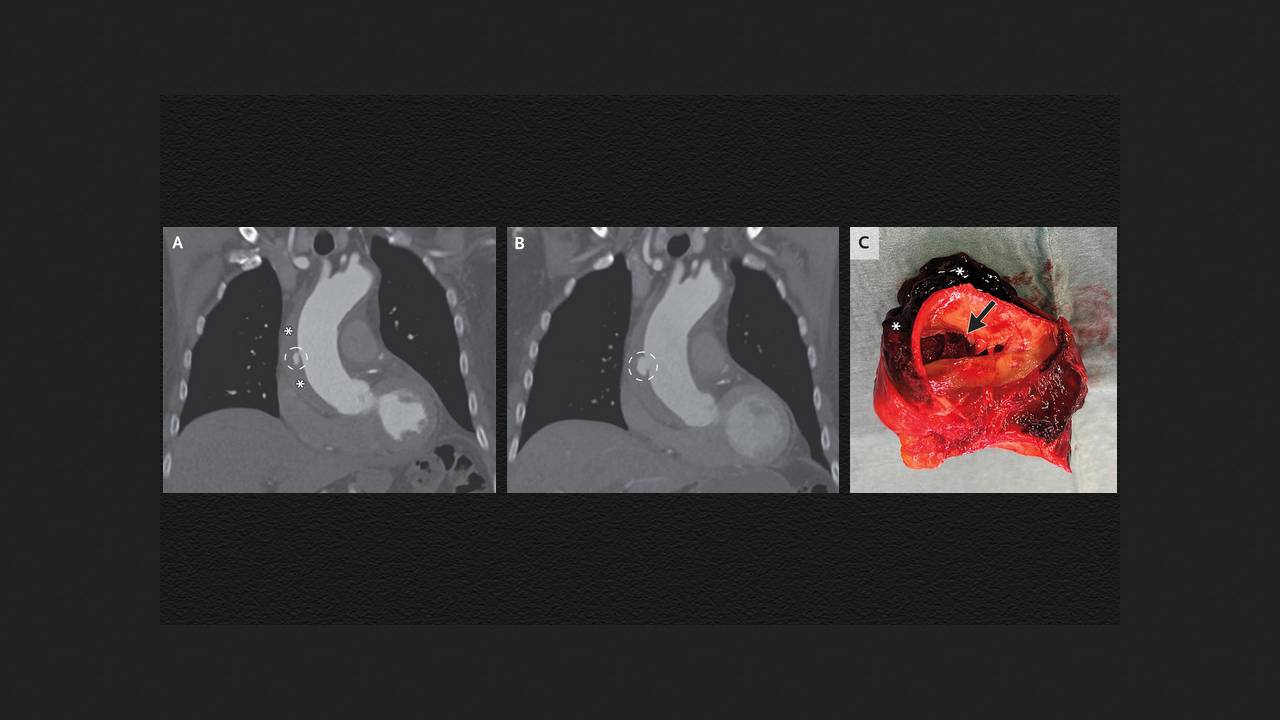

В неотложное отделение нидерландской больницы поступил 80-летний мужчина без особенностей в анамнезе с жалобами на боль в грудной клетке в течение 12 часов и повышением уровня D-димера (маркера недавнего тромбоза). Его артериальное давление было 147/92 миллиметра ртутного столба, пульс — 70 ударов в минуту, а данные осмотра — нормальными. Компьютерная томографическая ангиография легких не выявила тромбоэмболии легочных артерий, однако на ней были видны язвоподобное образование на восходящей аорте и внутристеночная гематома, которая распространялась на дугу и верхнюю часть нисходящей аорты. Врачи Шурд Баувместер (Sjoerd Bouwmeester) и Андре Тьон Юк Тьин (Andrew Tjon Joek Tjien) из Больницы Катарины в Эйндховене поделились этим случаем в The New England Journal of Medicine.

Мужчине поставили диагноз интрамуральной гематомы аорты — формы острого аортального синдрома, при которой кровь поступает в среднюю оболочку сосуда с формированием тромба, выпячивающего сосудистую стенку наружу. Это состояние связано с повышенным риском расслоения аорты. Пациенту начали инфузионную терапию для снижения артериального давления и частоты сердечных сокращений. Боль в груди прошла, и его перевели в кардиологический центр. После беседы с пациентом врачи приняли решение не проводить неотложное хирургическое вмешательство и продолжить наблюдение. На КТ через три для наблюдалось увеличение язвоподобного образования, и мужчине выполнили открытую операцию по протезированию восходящей аорты над коронарными сосудами и половины дуги аорты. В иссеченном участке сосуда помимо гематомы обнаружили разрыв внутренней оболочки и расслоение восходящей аорты. Через шесть дней после операции пациента выписали из больницы.